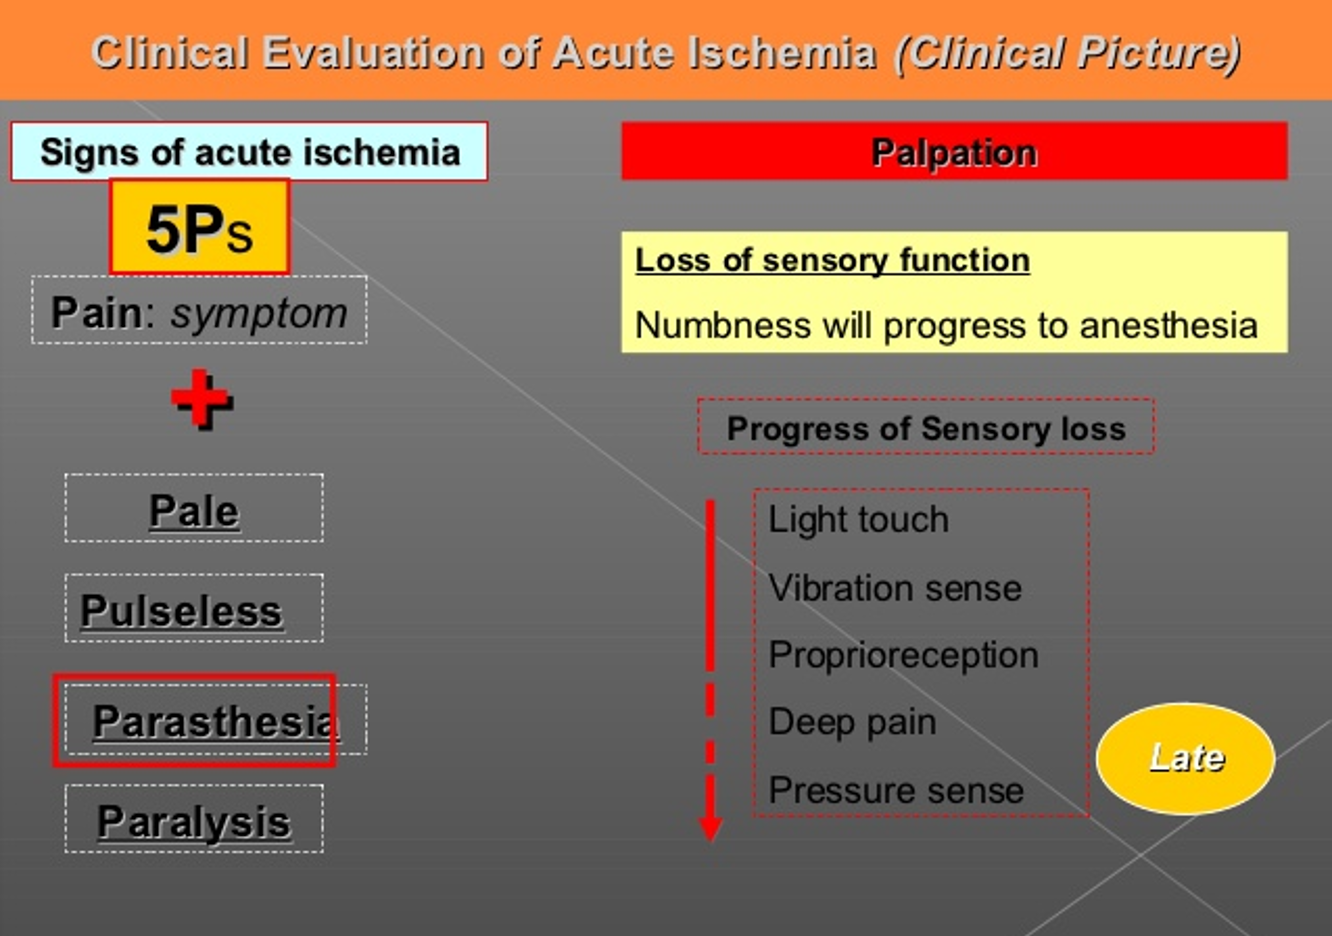

- Paresthesia

Early -⇒ Late

light touch ⇒ vibration ⇒ Proprioreception ⇒ Deep pain ⇒ Pressure sense Z

Early -⇒ Late

light touch ⇒ vibration ⇒ Proprioreception ⇒ Deep pain ⇒ Pressure sense Z